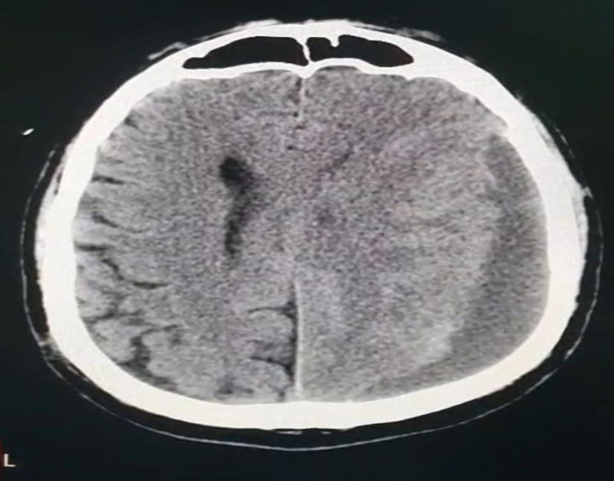

The patient recalled a car accident three months prior, during which he might have sustained a head injury, but no imaging study was performed at that time. This context made us reconsider his symptoms, and a brain CT was performed, showing a left subdural hematoma (Figure 1).

Figure 1: Non-contrast brain CT demonstrating a left chronic subdural hematoma. The axial section shows a crescent-shaped, hypodense collection along the left cerebral hemisphere, consistent with chronic subdural hematoma, causing mild mass effect and midline shift.